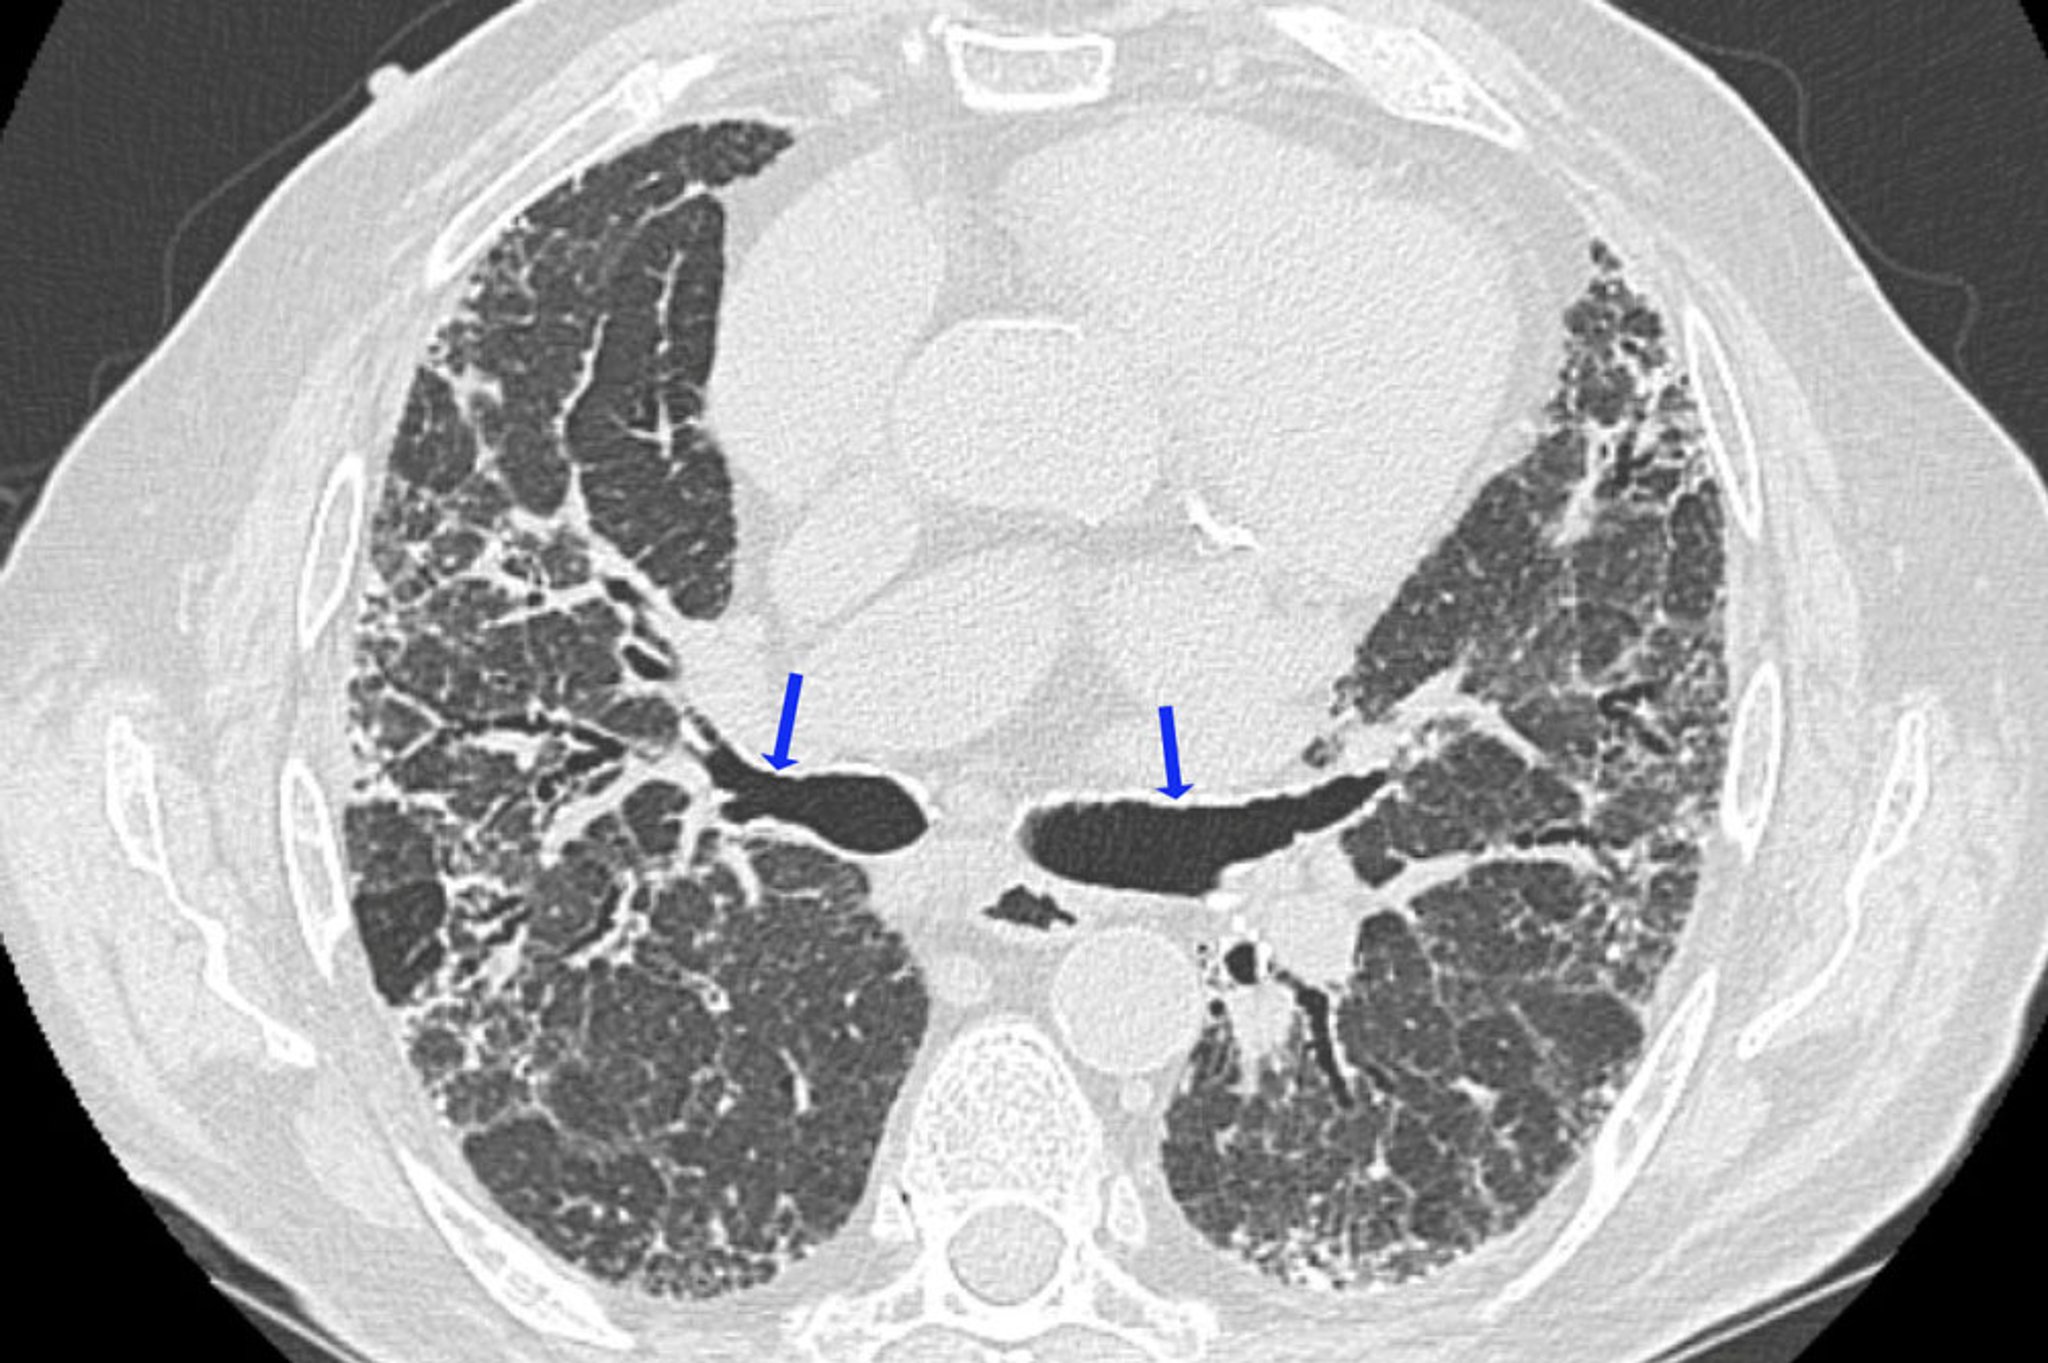

This high-resolution CT scan shows findings of fibrosis, including irregular reticulation and traction bronchiectasis (arrows). Areas of decreased lung density are compatible with regions of airway obstruction. This combination of findings is suggestive of hypersensitivity pneumonitis.

Image courtesy of Joyce Lee, MD, MAS.